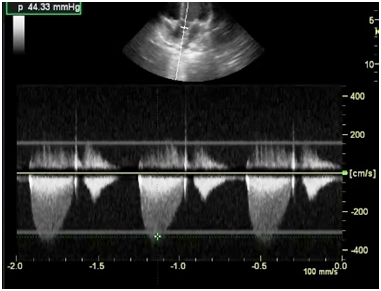

Investigations revealed hemoglobin value of 9g/dL, WBC count 4,000/cumm and platelet count was normal. Liver function test and renal function tests were normal. ECG showed the left ventricular hypertrophy. On chest X-ray there was a normal cardiac silhoutte and a normal lung parenchyma. Transthoracic echocardiography showed parachute-like mitral valve with a severe mitral stenosis (mitral valve size: 0.6 cm2, pressure gradient (Pg: 20 mmHg) causing obstruction to flow Figure 1. Aortic valve was bicuspid with a mild to moderate aortic stenosis (Pg: 40 mm Hg) Figure 2. Severe post-ductal coarctation of aorta with a diastolic tailing was seen on suprasternal view Figure 3. There was a Tiny mid muscular ventricular septal defect with left to right shunt. Small size patent ductus arteriosus with bidirectional shunt mainly left to right was present. Severe tricuspid regurgitation secondary to severe pulmonary hypertension (Right Ventricular systolic pressure = 84mmHg). Pulmonary artery was grossly dilated. There was mild left ventricular hypertrophy with a normal global systolic function and a normal ejection fraction. CT angiography revealed post ductal coarctation of aorta with patent ductus arteriosus with enlarged pulmonary trunk.

Figure 1B Continuous wave doppler studies demonstrated increased peak early (e) and late atrial (a) diastolic flow velocities, peak e-wave velocity is increased, 2.3 m/s.